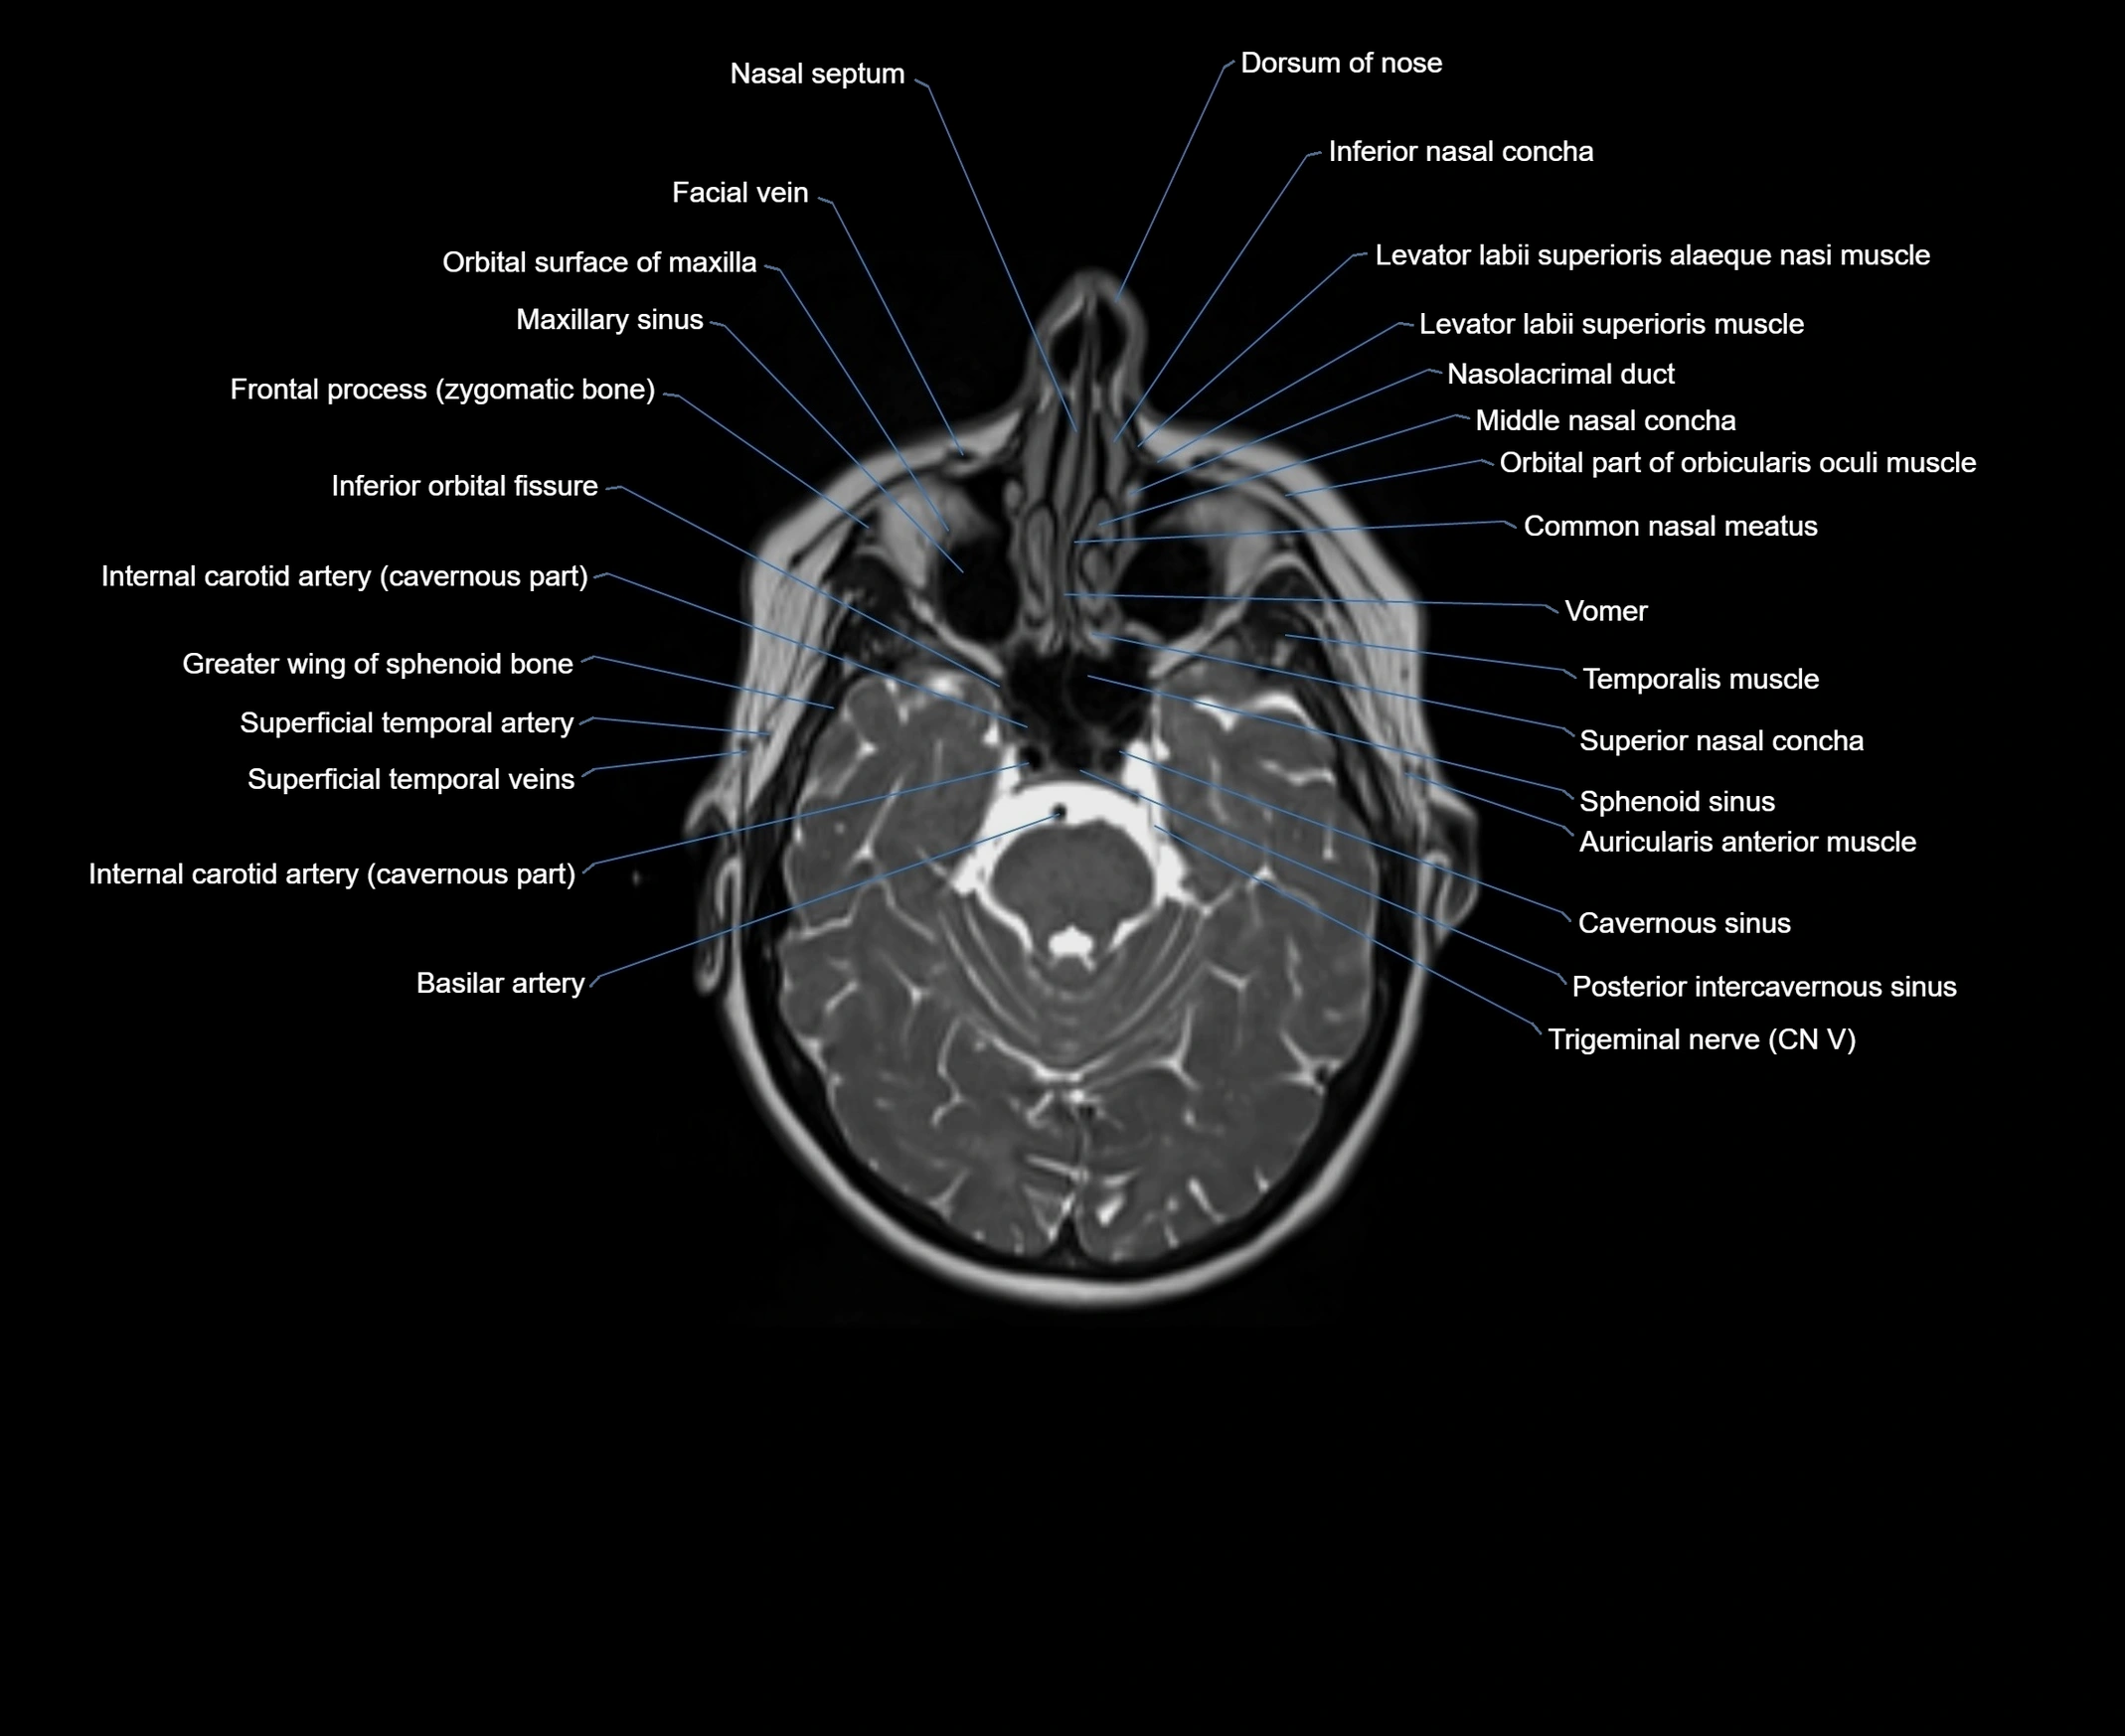

- Common nasal meatus

- Dorsum of nose

- Facial vein

- Frontal process (zygomatic bone)

- Greater wing of sphenoid bone

- Inferior orbital fissure

- Internal carotid artery (cavernous part)

- Middle nasal concha

- Nasal septum

- Nasofrontal vein

- Nasolacrimal duct (Tear duct)

- Sphenoid sinus

- Superior nasal concha

- Trigeminal nerve (Cranial nerve V)